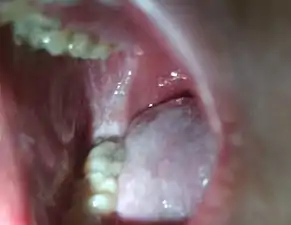

Koplik's spots seen inside the mouth are diagnostic for measles, but are temporary and therefore rarely seen.[21] Koplik spots are small white spots that are commonly seen on the inside of the cheeks opposite the molars.[20] They appear as "grains of salt on a reddish background."[23] Recognizing these spots before a person reaches their maximum infectiousness can help reduce the spread of the disease.[24]

Koplik's spots on the third pre-eruptive day

Koplik's spots on the day of measles rash.